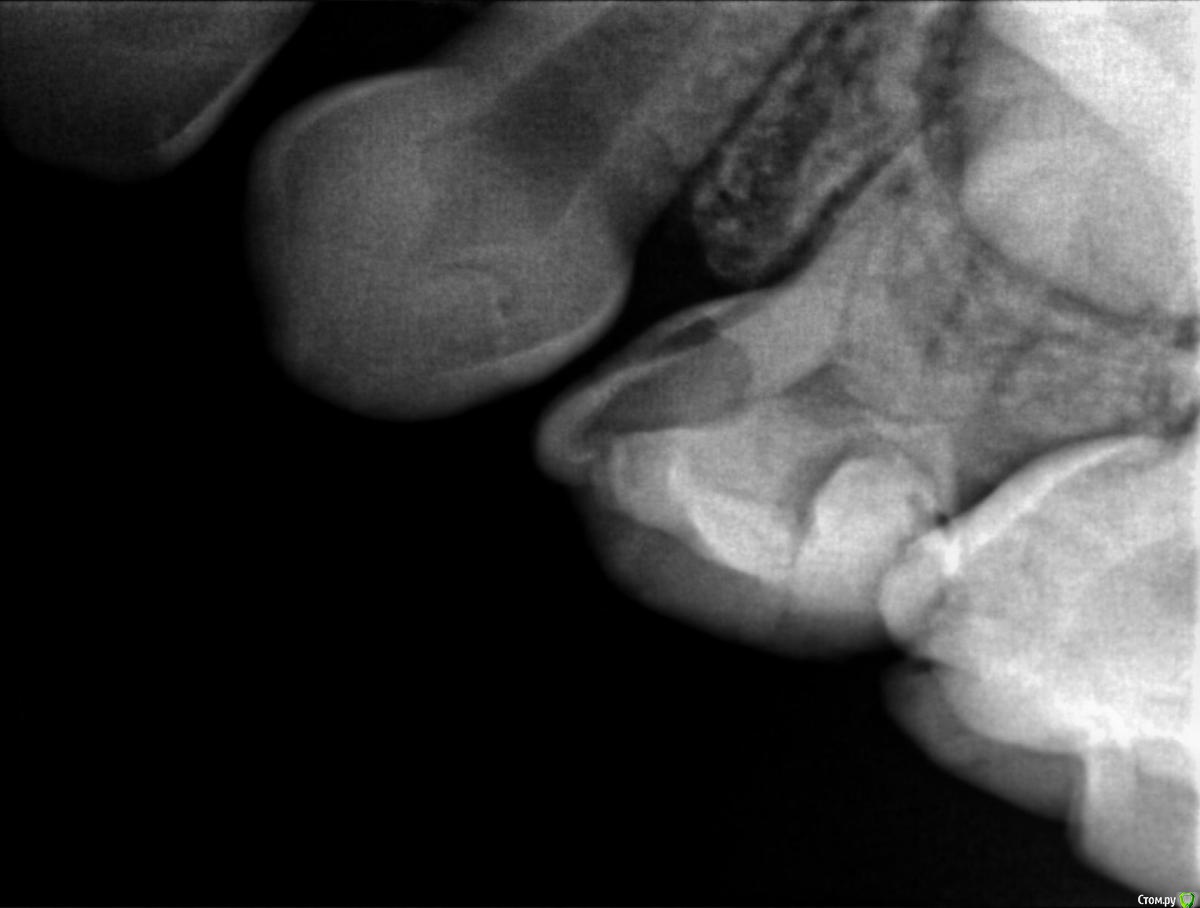

Пошли к врачу, сделали рентген и на рентгене видно что начал образовываться кариес почти на всех молярах, либо под пломбами, либо на стыке зубов. Так как зубы уже леченые доктор говорит что лечить дальше смысла нет, пломба держаться не будет, выпадет снова, предлагают ставить коронки сразу на все моляры, а зуб где уже большая пломба (зуб I на ренгене) просто удалить (не болит) и поставить space mantainer + удалить зуб А.

На всякий случае прикрепляю снимки, буду рад услышать мнение.